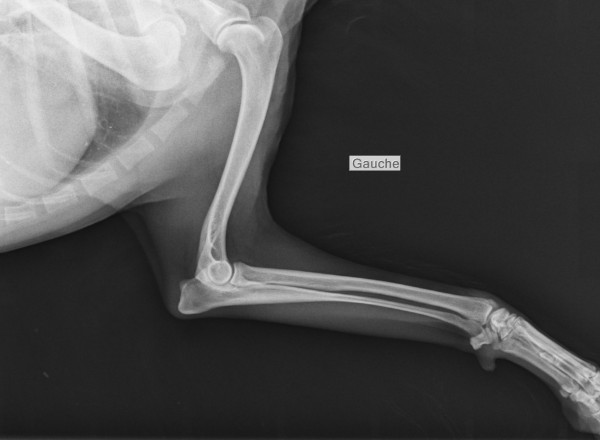

Radiographie Numérique

Radiographie Numérique Sedecal Vet

avec ou sans sédation , suivi radiologique ,